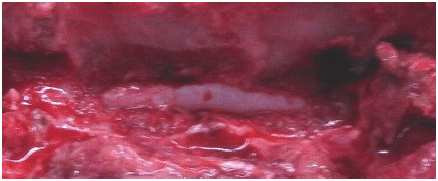

手術中の写真です。 神経が下から押され潰されているところです。 |

椎間板を取り除いた後の写真です。 神経が正常な位置に戻りました。 |